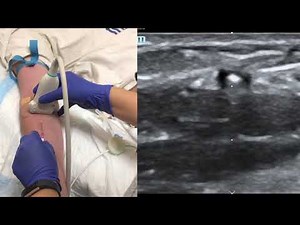

Effect - Ultrasound Peripheral IV

Insertion CEU - Ultrasound-Guided IV

Made Easy - Mammogram

-Guided IV - Longitudinal View

Placement - Ultrasound-Guided IV

in the Neck - IV